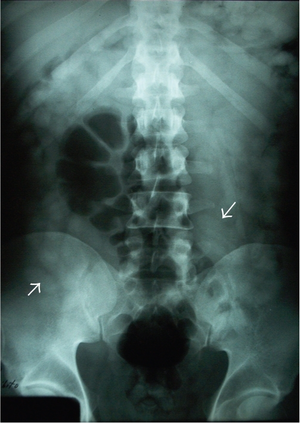

Body-packing with multiple foreign bodies ("balls" of hashish) on KUB

Narcotics Ingestion (i.e. Body Packing)

- Multiple packets inserted in latex bags, ingested to cross borders

- Each packet potentially toxic if bag bursts

- Consider whole-bowel irrigation

- Endoscopy contraindicated (high % leakage/rupture of packets)

- Surgical removal indicated if evidence of systemic toxicity

- Do not discharge until all packets removed or 3 packet-free stools